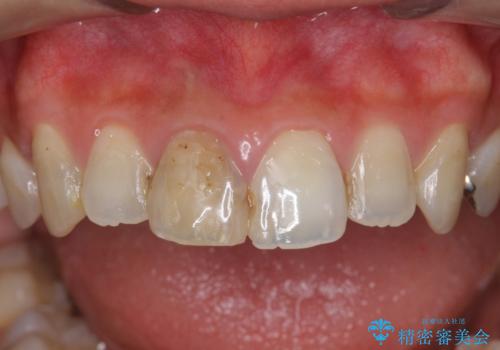

前歯 審美改善セラミック治療

- 前歯の見た目、変色の改善を希望され来院されました。

ジルコニアクラウンによる審美性の改善を計画します。

- 24万円(仮歯・ファイバーコア・ジルコニアクラウン)費用は治療当時の料金となります